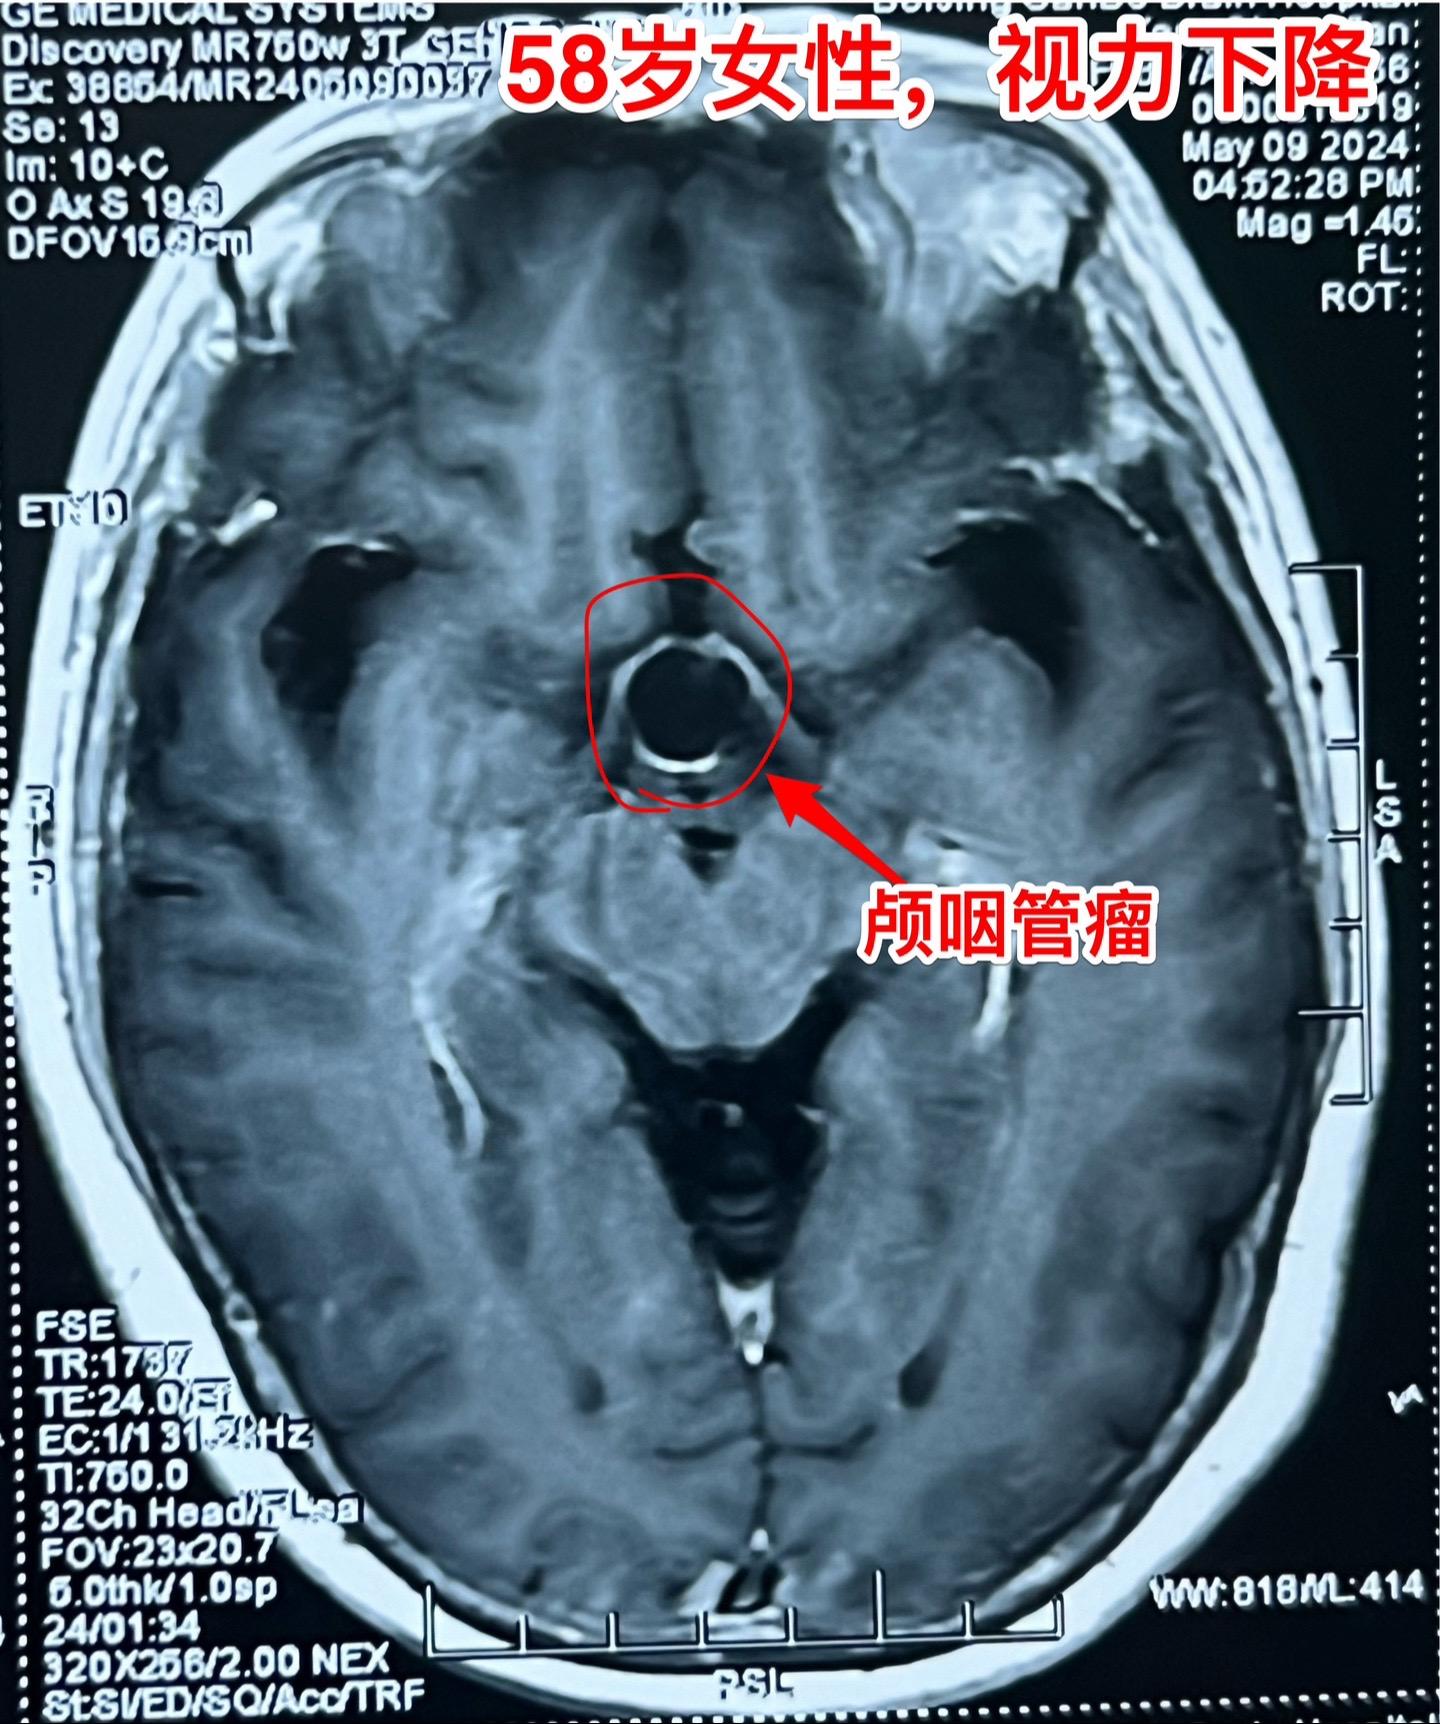

58岁女性视力下降。这是典型的颅咽管瘤。 这样的颅咽管瘤更适合翼点入路:瘤位于鞍上池内,直径约2厘米,乳头型颅咽管瘤。 病人的左眼视力更差,所以选择经左侧翼点入路。肿瘤得到完全切除。视力下降

58岁女性视力下降。这是典型的颅咽管瘤。 这样的颅咽管瘤更适合翼点入路:瘤位于鞍上池内,直径约2厘米,乳头型颅咽管瘤。 病人的左眼视力更差,所以选择经左侧翼点入路。肿瘤得到完全切除。颅咽管瘤视力下降